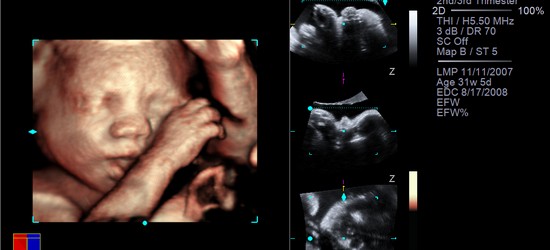

NVIDIA и Siemens Healthcare недавно продемонстрировали новую технологию ультразвукового 3D сканирования, которая позволяет будущим родителям и акушерам увидеть плод с высоким уровнем детализации с помощью 3D-очков.

Благодаря пришедшей из 3D-фильмов технологии новое программное обеспечение для обработки изображений Siemens fourSight Workplace использует стереоочки NVIDIA 3D Vision и профессиональную графику высокого уровня NVIDIA Quadro FX для создания впечатляющих 3D/4D изображений еще не родившегося ребенка.

Изображения, полученные с помощью ультразвуковой системы ACUSON S2000, проходят дальнейшую обработку в программе Amnioscopic Rendering от Siemens, которая воспроизводит фотореалистичное 3D-изображение плода.